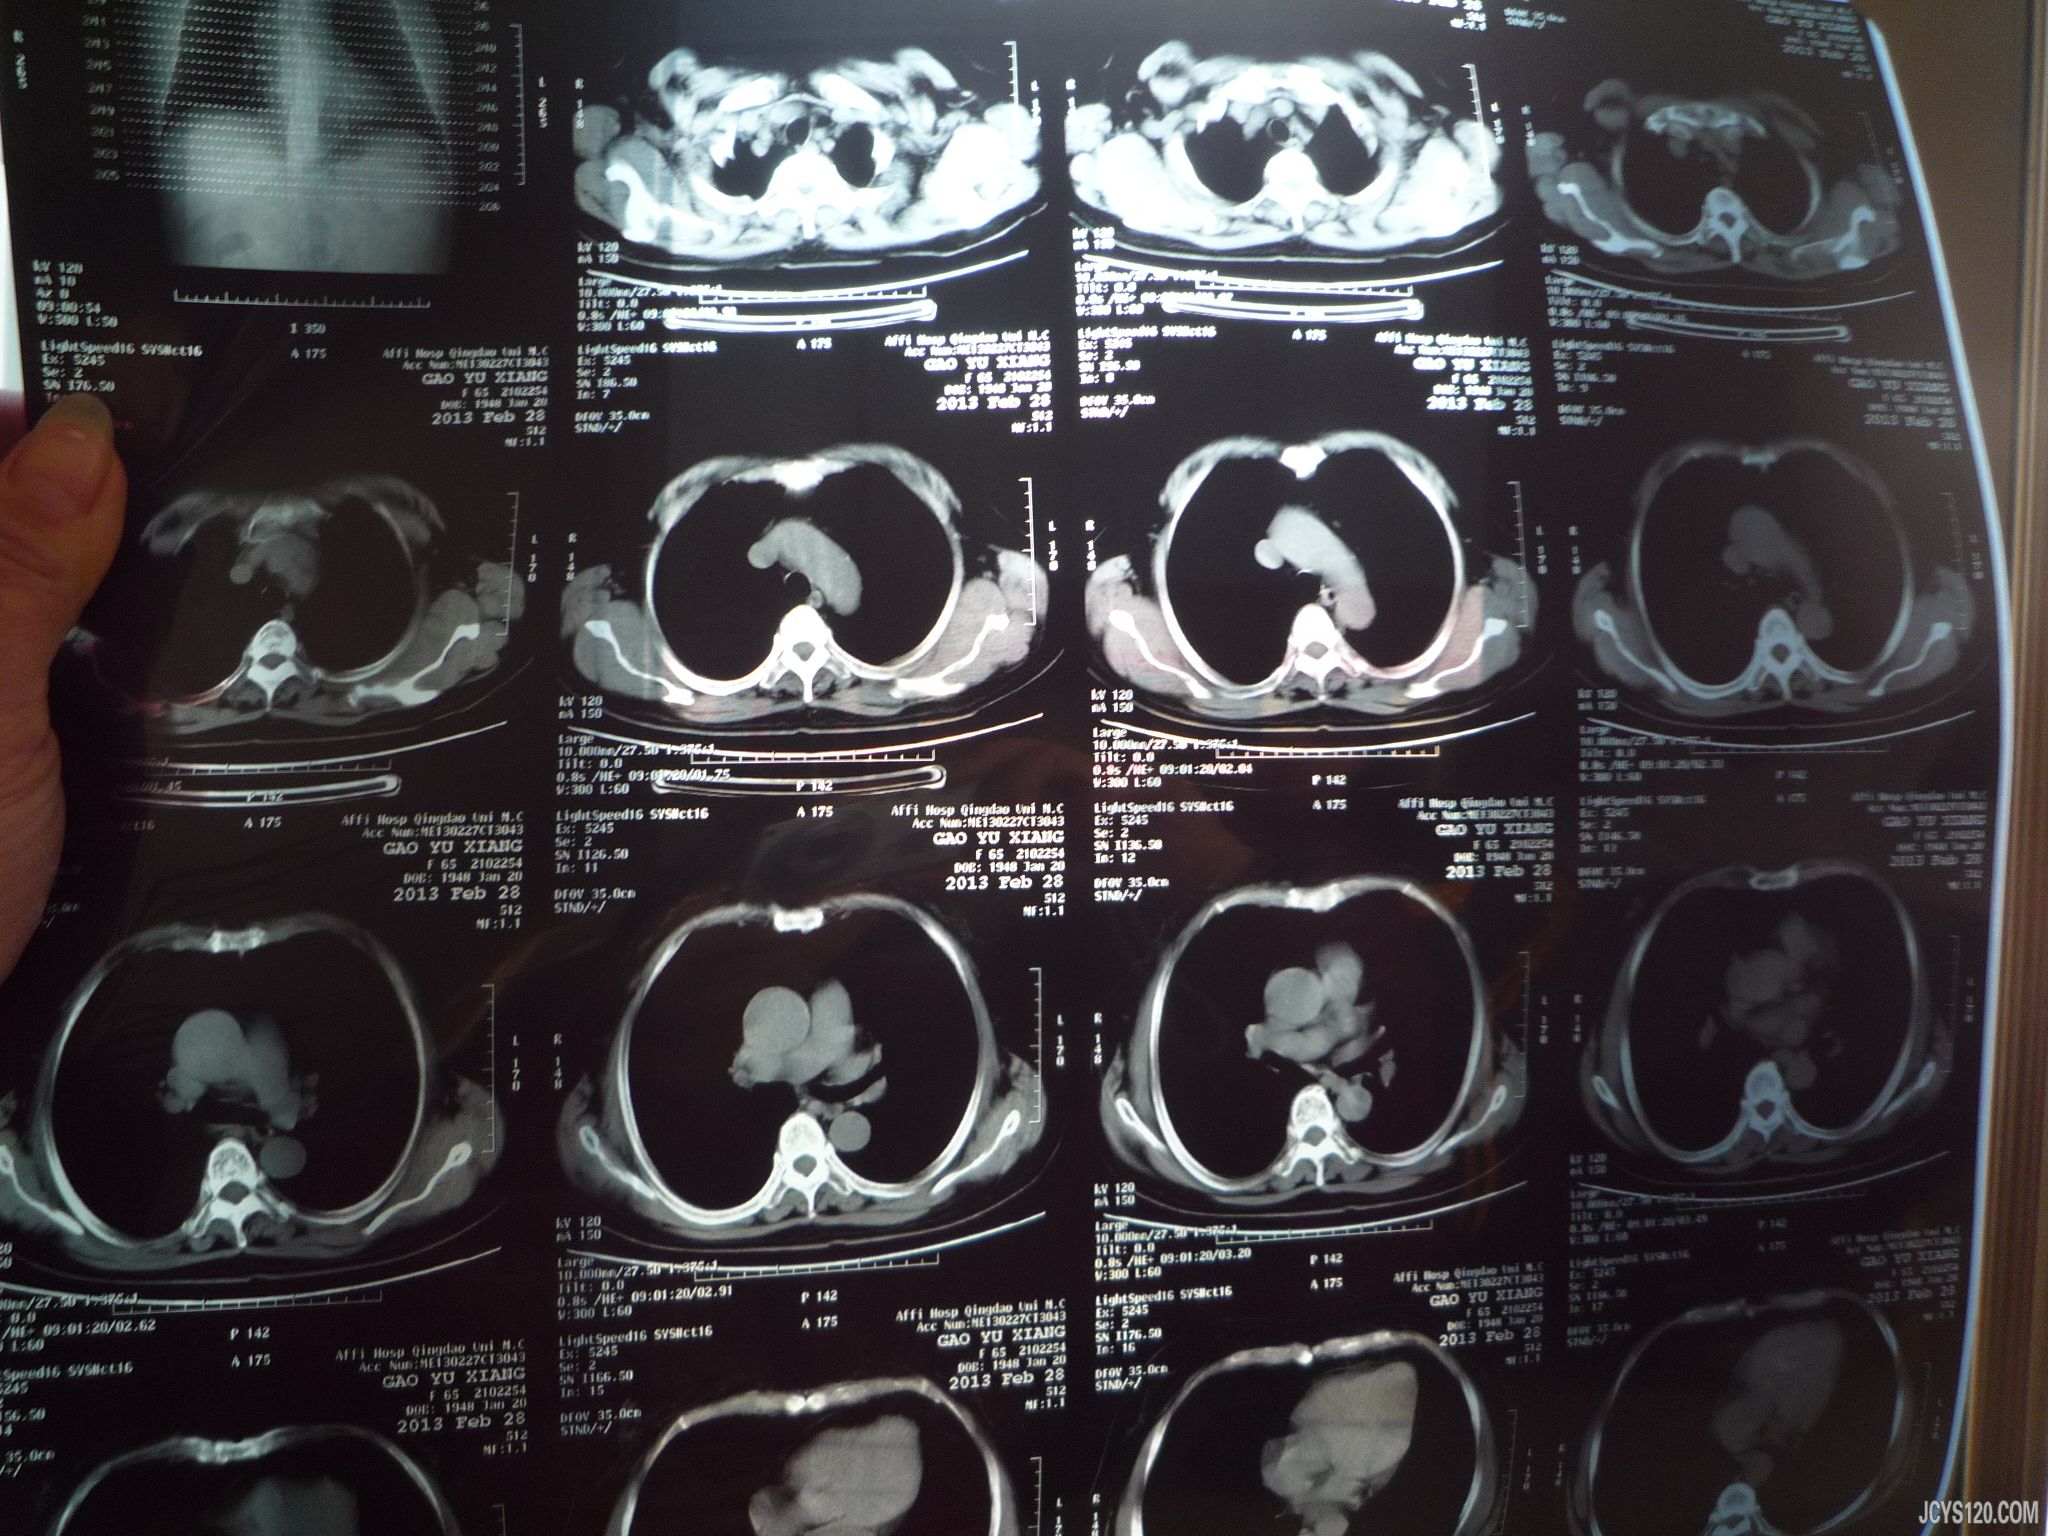

主诉:咳嗽咳血一个月

现病史:一个月前患者咳嗽,时轻时重,在家自行口服药物,具体药物不详,咽干咽痒,咳嗽时感觉胸部不适,咳嗽厉害还吐痰,痰中带有鲜血,一共吐了3次血痰,量不多,无发热,无恶心呕吐,无头疼头晕,咳嗽期间输液治疗3天(克林霉素 )感觉咳嗽减轻,停止输液,口服药物。中途去医院检查2次。

县医院检查结果和市医院检查结果 不一样:

以上是患者的一般情况及2次医院就诊检查结果,县医院检查和市医院不一样,大家看看此患者属于什么情况?